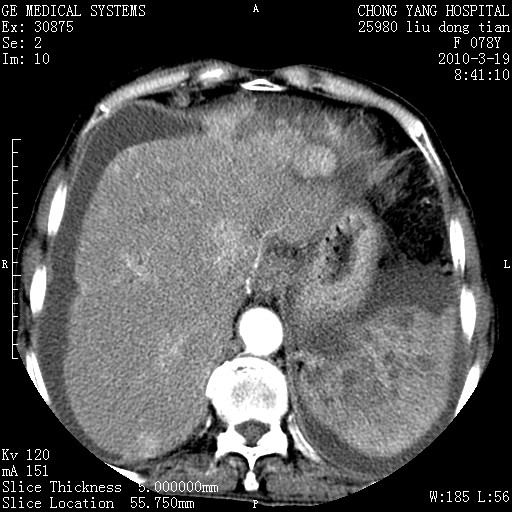

标题: CT25199:F 78Y 腹胀半年 消瘦乏力 [打印本页]

标题: CT25199:F 78Y 腹胀半年 消瘦乏力

胆囊壁增厚并明显强化,胆囊癌伴多发转移瘤可能性大,淋巴瘤不除外,右肾囊肿,胸腹水.

考虑nhl,肝、脾、腹膜腔及腹膜后多发淋巴结受侵,腹水,右肾囊肿,慢性胆囊炎,右侧少量胸腔积液。

胰头有肿块形成,胰头ca伴肝脾、腹膜腹膜后转移

胆囊有软组织影有强化,支持胆囊癌,肝脾、腹膜后淋巴结转移。

nhl的淋巴结多围绕主动脉,而且主动脉会移位,所以不考虑nhl。

分开来讲:肝左叶、尾叶病灶有不均强化像肝癌;

脾脏病灶无强化,像多发囊肿或淋巴管瘤,不除外淋巴瘤(低强化);

胆囊增生性病变:胆囊癌,腺肌增生症,慢性胆囊炎;

肝门、胰腺头、腹膜后多个团块: 淋巴瘤,转移;

腔静脉肝内段细小有无布加可能?

一元论最好了 淋巴瘤所致改变; 胆囊癌转移不像,胆囊周围肝组织清晰,肝癌淋巴结转移?三元论都不止。

胰头ca伴肝脾、腹膜腹膜后转移!

最后报的胰头癌多发转移,脾脏单独考虑囊肿或淋巴管瘤。